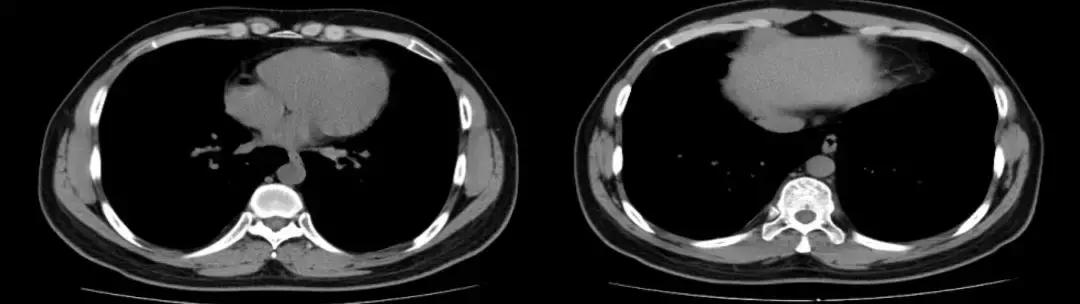

复查胸部CT(2018-1-29),对比原片如下图:

1、两肺野弥漫病变较前未见明显变化,两肺上叶陈旧病变同前

2、左肺下叶片状密度增高影较前范围增大,密度增高

3、纵膈内多发淋巴结,大者位于气管隆突下,短径约1.1cm,较前未见明显变化;余基本同前。

复查胸部CT(2018-07-12):

左肺炎症较前好转,但肺部弥漫性病变较前变化不大。